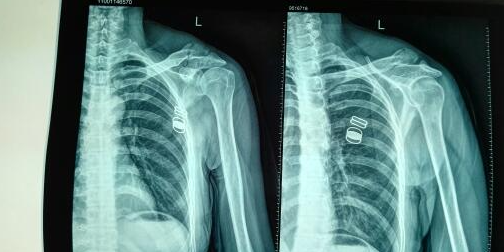

首先,患者接受了CT掃描,杭州博型科技利用這些數(shù)據(jù)進行三維重建,生成了患者肱骨的精確三維模型。這使得醫(yī)生能夠更清晰地了解骨折的具體情況,為手術制定了詳細的預案。同時,杭州博型科技還利用3D打印技術制作了患者肱骨的實體模型,以便醫(yī)生在手術前進行模擬手術。

在充分了解患者骨折情況和預演手術過程后,醫(yī)生采用了個性化的矯形工具,進行了精確的手術治療。術后患者的恢復進展順利,手術效果顯著。這一案例充分展示了杭州博型科技的3D打印和CT重建技術在肱骨大結節(jié)骨折治療中的優(yōu)勢。